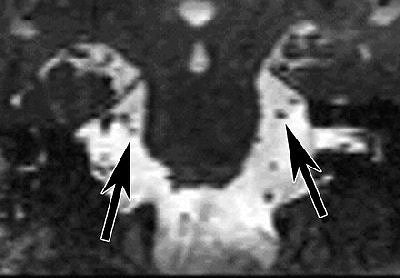

![]() |

| Coronal reformatted image of the brain. Constructive interference in steady state (CISS) MR image (17/8.3) at the level of the ambient cistern reveals trigeminal nerve on right (left arrow) is smaller than trigeminal nerve on left (right arrow). Figure 1, Erbay SH, Bhadelia RA, O'Callaghan M, et al. "Nerve atrophy in severe trigeminal neuralgia: Noninvasive confirmation at MR imaging -- initial experiences." Radiology 2006; 238:689-692. |

Even the most sophisticated imaging exam can't necessarily distinguish between normal and abnormal vessel-nerve contact, according to Dr. Sami Erbay, a neuroradiologist at Lahey Clinic in Burlington, MA, and Tufts-New England Medical Center in Boston.

"The vessel and the nerve can be close to each other and contacting in normal people as well," Erbay said. "That makes it difficult for the imagers to see which one is an innocent contact, and which one is more severe neurovascular compression leading to trigeminal neuralgia."

However, Erbay said that he believes visible TN markers do exist, and he's currently engaged in an ongoing trial to confirm TN with MRI. Erbay and colleagues published some early results of their work last year and found that trigeminal nerve atrophy can be depicted noninvasively with gadolinium-enhanced MRI (Radiology, February 2006, Vol. 238:2, pp. 689-692).